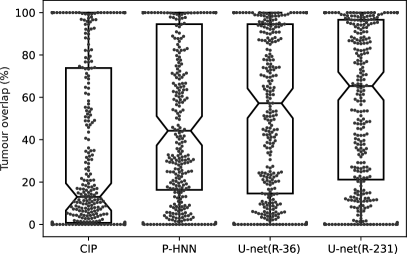

Models trained on routine data achieve improved evaluation scores compared to models trained on publicly available study data. U-net, ResU-net, and Deeplab v3+ models, when trained on routine data (R-36), yielded the best evaluation scores on the merged test dataset (All, n = 62). The U-net yields mean DSC, HD95, and MSD scores of 0.96 0.08, 9.19 18.15, 1.43 2.26 when trained on R-36 [U-net(R-36)] and 0.92 0.14, 13.04 19.04, 2.05 3.08 when trained on VISC-36 (R-36 versus VISC-36, p = 0.001, 0.046, 0.007) or 0.94 0.13, 11.09 22.9, 2.24 5.99 when trained on LTRC-36 (R-36 versus LTRC-36, p = 0.024, 0.174, 0.112). This advantage of routine data for training is also reflected in results using other combinations of model architecture and training data. Table III lists the evaluation results in detail. We determined that the influence of model architecture is marginal compared to the influence of training data. Specifically, the mean DSC does not vary for more than 0.02 when the same combination of training and test set was used for different architectures (Table III). Compared to readily available trained P-HNN model, the U-net trained on the R-231 routine dataset [U-net(R-231)] yielded mean DSC, HD95, and MSD scores of 0.98 0.03, 3.14 7.4, 0.62 0.93 versus 0.94 0.12, 16.8 36.57, 2.59 5.96 (p = 0.024, 0.004, 0.011) merged test dataset (All, n = 62). For comparison with the CIP-algorithm, only volumes for which the algorithm did not fail were considered. On the merged dataset (All, N=62) the algorithms yielded mean DSC, HD95, and MSD scores of 0.98 0.01 ,1.44 1.09 ,0.35 0.19 for the U-net(R213) compared to 0.96 0.05, 4.65 6.45, 0.91 1.09 for CIP (p = 0.001, 0.001, 0.001). Detailed results are given in Table IV. Fig. 2 shows qualitative results for cases from the routine test sets and Fig. 3 shows cases for which the masks generated by the U-net(R-231) model yielded low DSCs when compared to the ground truth. We created segmentations for the 55 cases of the LOLA11 challenge with the U-net(R-231) model. The unaltered masks yielded a mean overlap score of 0.968 and with dense areas removed 0.977. Table V and Fig. 4 show results for tumour overlap on the 318 volumes of the Lung1 dataset. U-net(R-231) covered more tumour volume mean/median compared to P-HNN (60%/69% versus 50%/44%, p 0.001) and CIP (34%/13%). Qualitative results for tumour cases for U-net(R-231) and P-HNN are show in Figs. 5b, c. We found that 23 cases of the Lung1 dataset had corrupted ground-truth annotation of the tumours (Fig. 5d). Fig. 5e shows cases with little or no tumour overlap achieved by U-net(R-231).

| Method | Mean (%) | Median (%) | ||

| CIP | 34 | 13 | 113 | 56 |

| P-HNN | 50 | 44 | 48 | 78 |

| U-net(R-36) | 53 | 54 | 46 | 79 |

| U-net(R-231) | 60 | 69 | 37 | 90 |